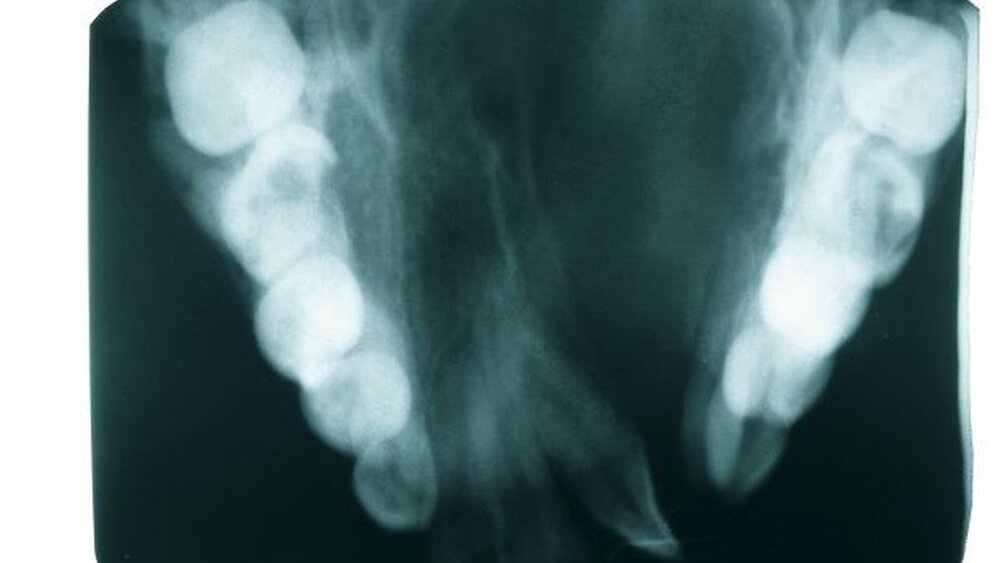

Die radiologische Untersuchung bestand aus einem Orthopantomogramm (OPTG), einer Aufbissaufnahme sowie einer Fernröntgenseitaufnahme (FRS). Neben der Übersicht der Gebissituation mit Nachweis des nicht durchgebrochenen Zahnes 22 im OPTG (Abbildung 3) war in der Aufbissaufnahme der Umfang der knöchernen Gaumenspalte klar zu erkennen (Abbildung 4). Das FRS ließ – bis auf die vertikal anterior verkürzte Maxilla und eine Protrusion der anterioren Prämaxilla – einen weitgehend normalen knöchernen Befund diagnostizieren (Abbildung 5).